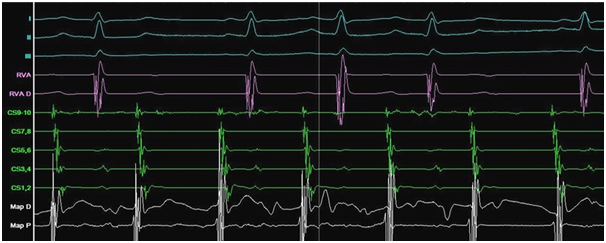

The ECG documented narrow complex short RP tachycardia with ventricular response of 140bpm. The patient noticed that around the time that the symptoms of palpitations appeared for the first time, she had lost the sense of smell and started to suffer from urinary incontinence but didn’t search for medical advice. She was assessed in our clinic and decision was made to proceed with electrophysiology study. The study showed dual atrio-ventricular (AV) node physiology. Supra-ventricular tachycardia (SVT) (Figure 1) was induced at a cycle length (CL) of 380ms with ventriculo-atrial interval of 35ms, and entrainment maneuvers supported typical AV node re-entry tachycardia as the working diagnosis. Slow pathway ablation was performed with successful outcome. During isuprel administration and atrial pacing incessant atrial tachycardia (AT) with two different CL of 360 and 320ms was provoked (Figure 2).

Figure 1 Typical atrioventricular nodal re-entry tachycardia (AVNRT).

Electrophysiological study: I, II, III- ECG leads; HRA- high right atrium; RVA- right ventricular apex; D- distal electrode, PR- proximal electrode; CS- coronary sinus.